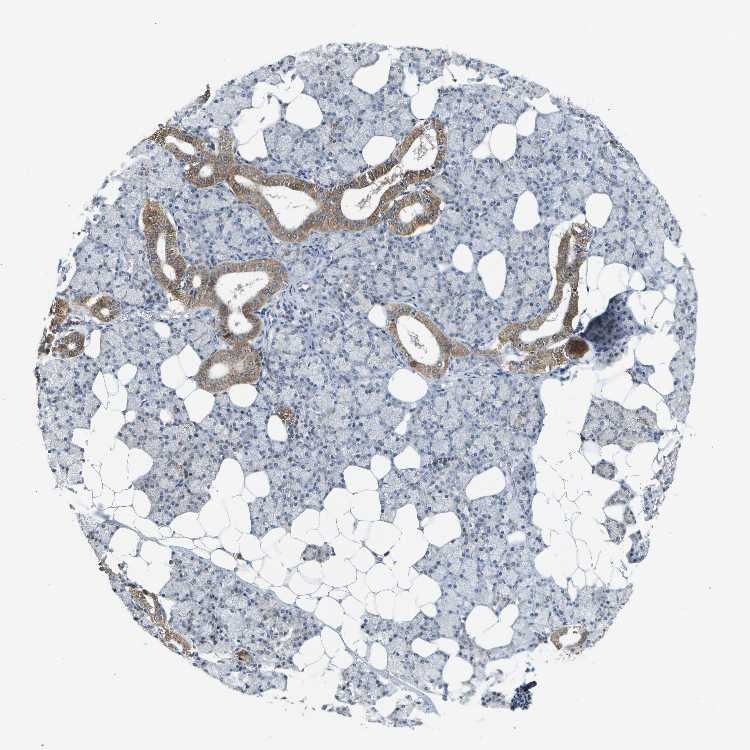

SALIVARY GLAND - Antibody stainingi

Antibody staining in the annotated cell types in the current human tissue is reported as not detected, low, medium, or high, based on conventional immunohistochemistry profiling in selected tissues. This score is based on the combination of the staining intensity and fraction of stained cells.

Each image is clickable and will lead to virtual microscopy that enables deeper exploration of all samples and also displays staining intensity scores, fraction scores and subcellular localization as well as patient and tissue information for each sample.

Antibody HPA015536

Glandular cells Medium